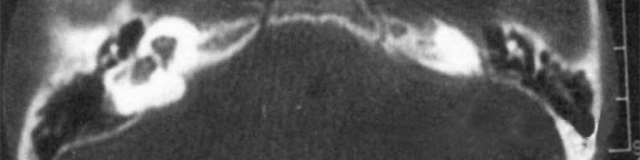

主要根據(jù)聽力學表現(xiàn)和影像學檢查。通過高分辨CT可看到耳蝸畸形。內耳MRI顯示膜迷路內水充盈,耳蝸扁平,耳蝸第二圈與頂圈間隔缺損,以及半規(guī)管、前庭的畸形。

先天性耳蝸畸形伴前庭和外半規(guī)管發(fā)育不良